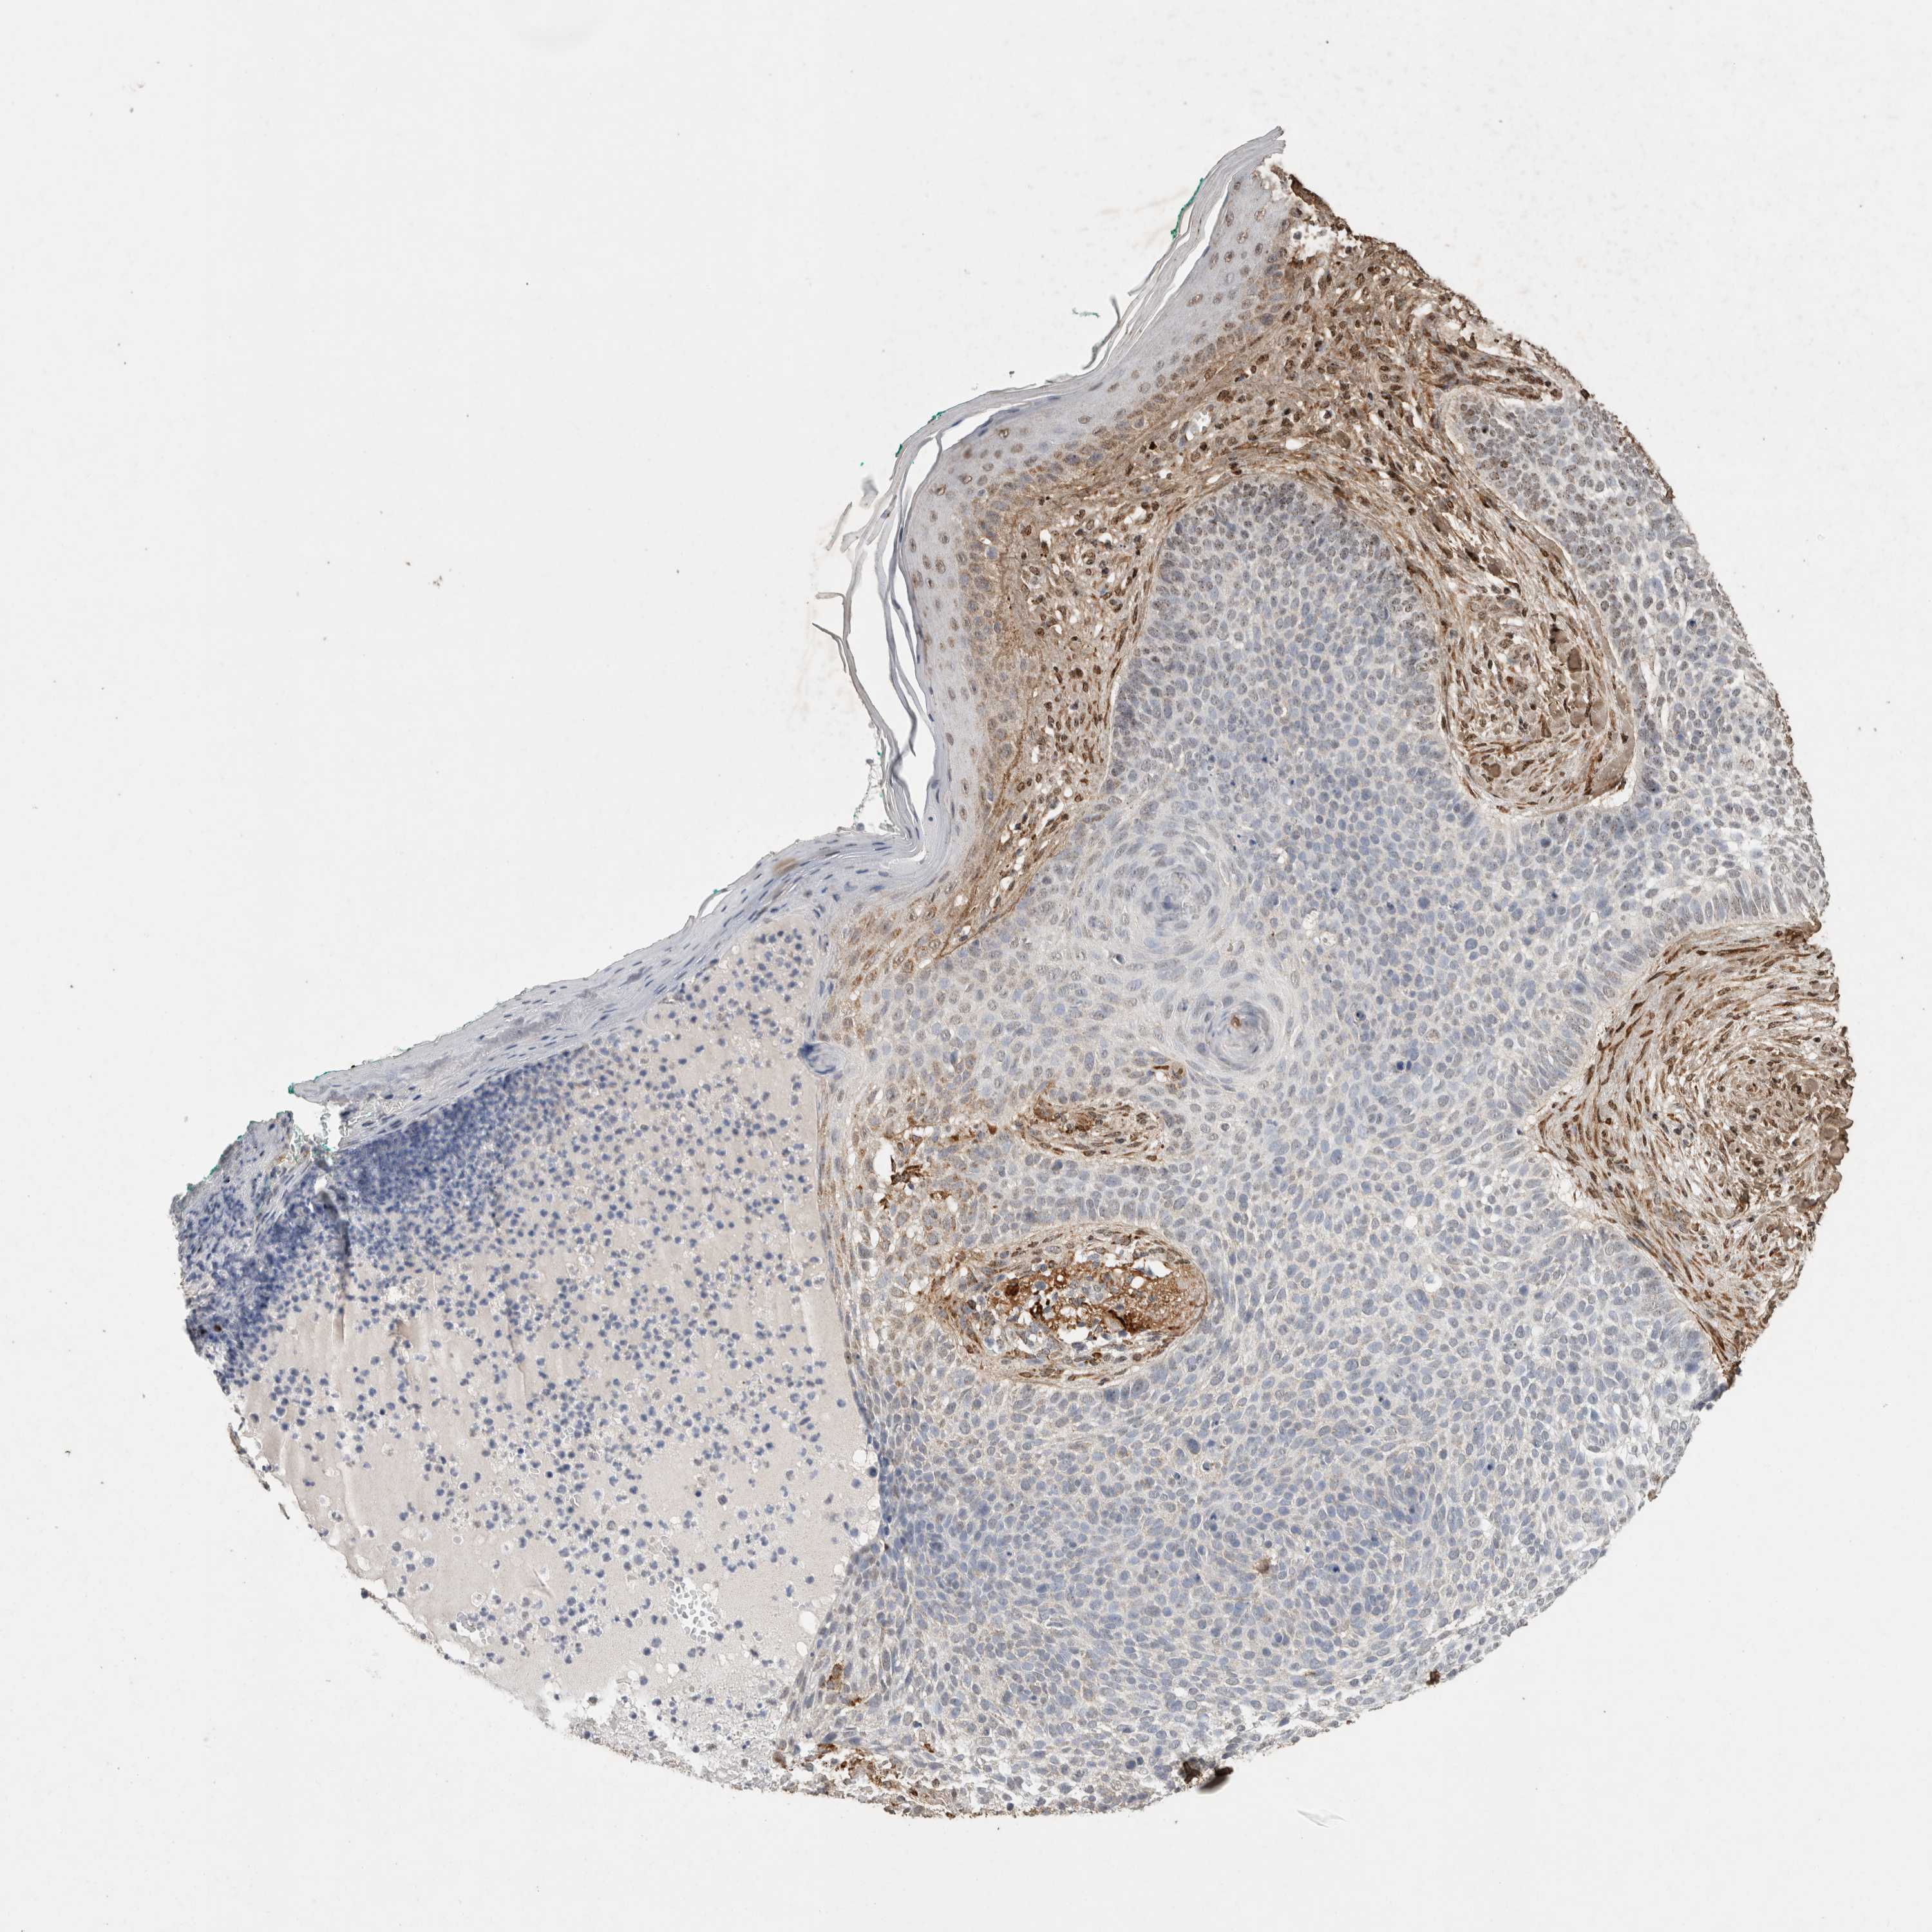

SKIN CANCER - Protein expressioni

A mouse-over function shows sample information and annotation data. Click on an image to view it in a full screen mode. Samples can be filtered based on level of antibody staining by selecting one or several of the following categories: high, medium, low and not detected. The assay and annotation is described here.

Antibody stainingi

Antibody staining in the annotated cell types in the current human tissue is reported as not detected, low, medium, or high, based on conventional immunohistochemistry profiling in selected tissues. This score is based on the combination of the staining intensity and fraction of stained cells.

Each image is clickable and will lead to virtual microscopy that enables deeper exploration of all samples and also displays staining intensity scores, fraction scores and subcellular localization as well as patient and tissue information for each sample.

Antibody HPA038604

Antibody CAB025607

Staining

High

Medium

Low

Not detected

Intensity

Strong

Moderate

Weak

Negative

Quantity

>75%

75%-25%

<25%

None

Location

Nuclear

Cytoplasmic/membranous

Cytoplasmic/membranous,nuclear

Basal cell carcinoma

Squamous cell carcinoma, NOS

Squamous cell carcinoma, metastatic, NOS